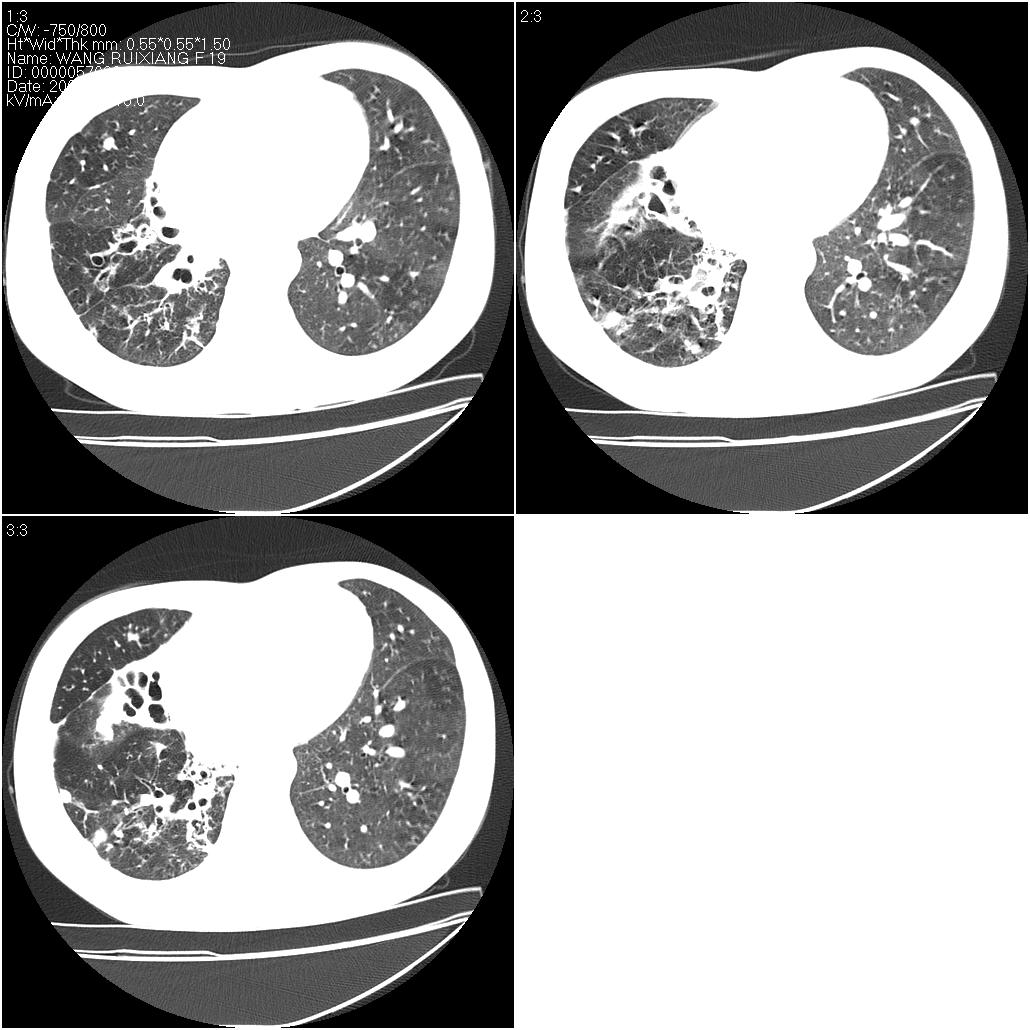

片子上的年龄为19岁,是操作错误。该患者于去年5月份曾做平片和ct扫描,和这一次的ct检查没有明显变化。当时诊断为肺结核,进行抗痨治疗至今,但没有改善。呼吸功能试验为混合型呼吸困难。除此之外,该患者没有其他方面没有的临床症状和体征

两肺见斑点片状阴影,部分病灶密度较高,右下肺见小囊状及柱状蜂窝状阴形,考虑为两肺结核以阵旧性为主,右下肺支扩。

1)两肺继发性肺结核(以增殖病灶为主)。2)两肺下叶支气管扩张。

1)两肺继发性肺结核(以增殖病灶为主)。

2)两肺下叶支气管扩张。

考虑肺淋巴管肌瘤病。

结合病人年龄(特别是生育期妇女)及临床表现多考虑淋巴管肌瘤病。